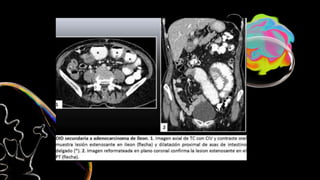

Asas dilatadas, colapsadas

o de calibre normal

Engrosamiento con

hipocaptacion de la pared

Ingurgitacion de vasos

mesentéricos

Obstrucción en asa cerrada

Colapso intestinal

Gas en sistema portal o

neumoperitoneo